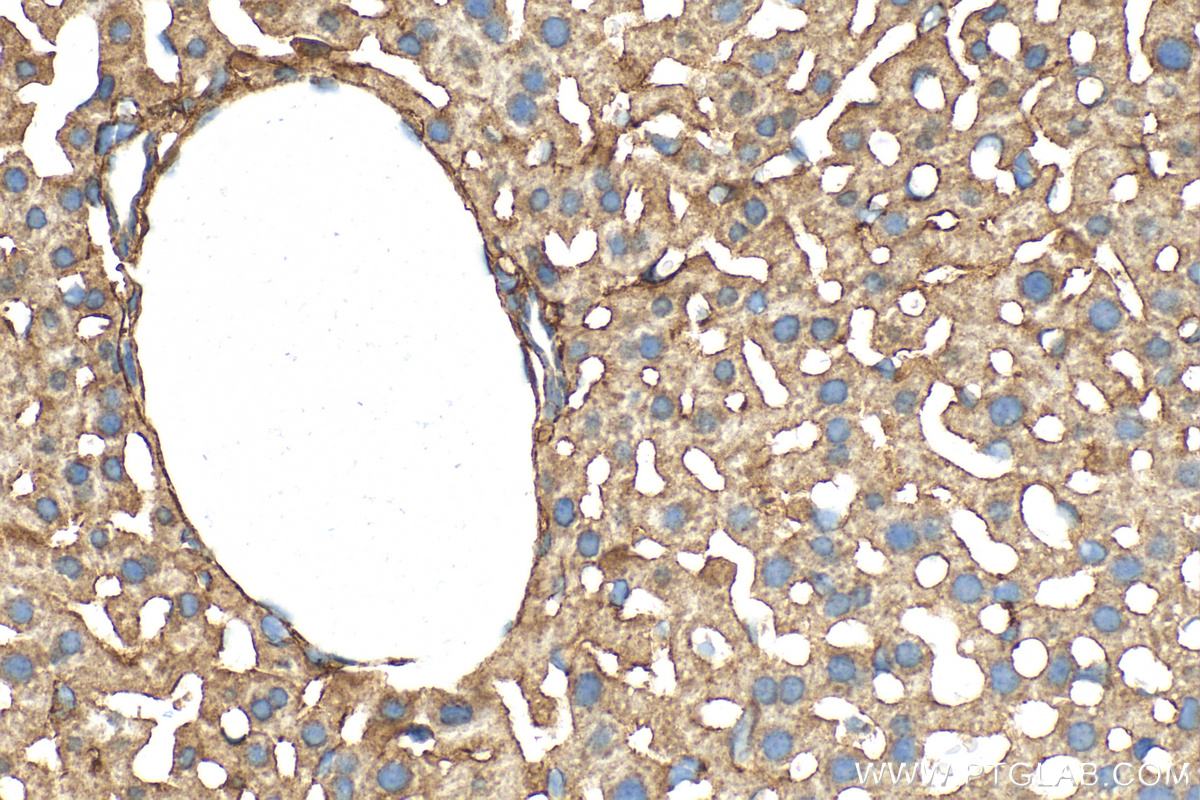

| Positive IHC detected in | human appendicitis tissue, mouse liver tissue, human urothelial carcinoma tissue Note: suggested antigen retrieval with TE buffer pH 9.0; (*) Alternatively, antigen retrieval may be performed with citrate buffer pH 6.0 |

| Immunohistochemistry (IHC) | IHC : 1:500-1:2000 |